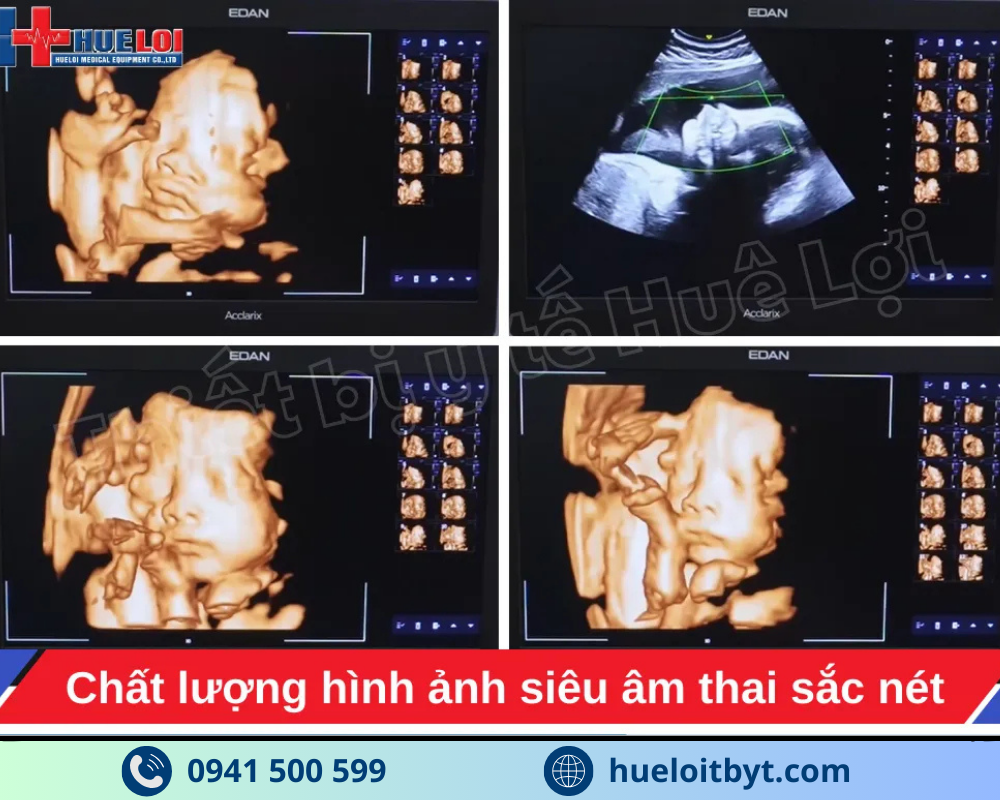

Máy siêu âm Edan LX85 ứng dụng nhiều công nghệ cải thiện chất lượng hình ảnh tiên tiến, cho phép hiển thị thai nhi sắc nét, chi tiết và chân thực ngay từ những tuần thai sớm. Nhờ độ phân giải cao và khả năng xử lý hình ảnh vượt trội, LX85 giúp bác sĩ sản phụ khoa dựng hình khuôn mặt thai nhi vô cùng sắc nét và tự nhiên, ứng dụng AI thông minh giúp tự động xóa những phần có thể che khuôn mặt em bé như nhau thai và tử cung, hỗ trợ chẩn đoán chính xác các bất thường trong thai kỳ. Đây là giải pháp siêu âm hiện đại, mang lại sự an tâm tối đa cho mẹ bầu và bác sĩ trong suốt hành trình theo dõi sản khoa.

Với mức đầu tư vô cùng hợp lý, mức giá của EDAN LX85 ở thời điểm hiện tại chỉ nằm trong khoảng hơn 350 triệu đồng cho cấu hình 3 đầu dò, máy siêu âm bàn đẩy EDAN LX85 đã phá vỡ mọi quy chuẩn trong phân khúc. Điểm nổi bật nhất phải kể đến là máy sở hữu những công nghệ cao cấp vốn chỉ có trên các hệ thống đắt tiền hơn nhiều, như công nghệ đàn hồi mô Shear Wave giúp đánh giá trực quan độ cứng tổn thương, công nghệ vi mạch Micro-Flow, và đặc biệt là công nghệ e-Live giúp tái tạo khuôn mặt thai nhi một cách tự nhiên và sắc nét. Sự kết hợp giữa mức giá cực tốt và hàng loạt tính năng chuyên sâu này đã định vị EDAN LX85 là một trong những hệ thống siêu âm bàn đẩy đáng đầu tư nhất trong phân khúc dưới 500 triệu đồng hiện nay.